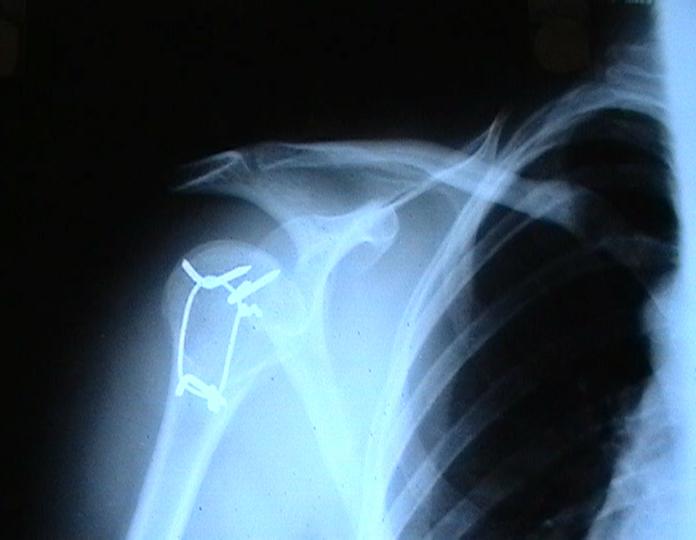

Мужчина 25 лет 16 августа 2002 г. в автоаварии получил перелом шейки плеча (снимок 1); 5 сентября в городской больнице выполнен остеосинтез пластинкой (снимок 2).К настоящему времени попал к нам на разработку ввиду выраженной контрактуры плечевого сустава. В течение последнего месяца беспокоят умеренные боли в области плечевого сустава, усиливающиеся при разработке, еще и торчит край пластинки. Нынешняя рентгенологическаякартина на снимках 3 и 4. Головка плеча уменьшается, сращение сомнительное.Кроме удаления пластинки, что еще на сегодня целесообразно сделать?Заранее спасибо.